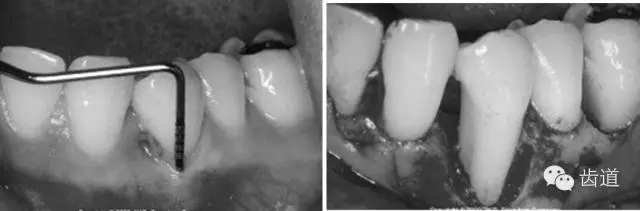

5、膜材料的邊緣位置和固位

原則是生物膜能充分覆蓋病損區(qū)。冠方緊鄰釉牙骨質(zhì)界,根方伸展至骨邊緣下 2~3mm,保證在組織愈合過(guò)程中能確切阻止口腔上皮和牙齦結(jié)締組織與牙根面接觸。

當(dāng)生物膜放置就位后,為防止受齦瓣的擠壓而移位后影響療效,應(yīng)用細(xì)線穿過(guò)生物膜的上部邊緣使之緊緊環(huán)抱牙齒,并采用懸吊縫合將其固定于牙面上。